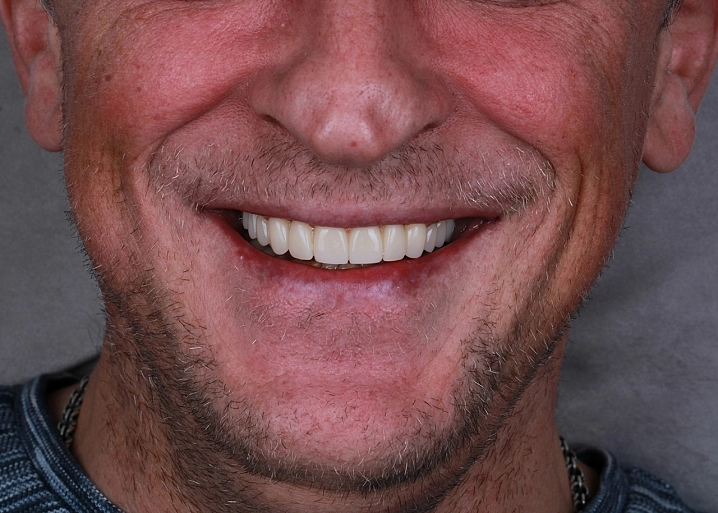

Проведена полная эстетическая реставрация зубных рядов верхней и нижней челюстей винирами E-max. Восстановлена форма, размер, цвет и поверхность фронтальных зубов, достигнута гармоничная улыбка.